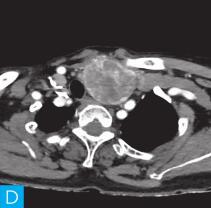

甲状腺CT检查:CT检查设备为256层iCT,病人采取仰卧位,扫描范围自外耳道平面至下颌角以下,常规扫描层厚为0.9mm、层间隔0.9mm,电压120kV,管电流280mA,矩阵512×512;经右肘静脉团注法增强扫描,碘海醇80ml,流速4ml/s,动脉期25秒扫描,静脉期60秒扫描。见图1。

图1 甲状腺CT

A、B.甲状腺CT横断面平扫;C~H.甲状腺CT横断面增强

CT平扫可见甲状腺左叶圆形以低密度为主病灶,大小为8.0cm×6.5cm,边界清晰,边缘尚光整,其内密度不均匀,低密度区CT值18HU,部分密度稍高,并可见斑点状粗大钙化影;CT增强后,甲状腺左叶病变呈不均匀渐进性强化,结节状改变,动脉期强化区CT值99HU,静脉期CT值85HU,且强化范围增大,提示该病变的血供较为丰富,应该考虑肿瘤样病变,结节性甲状腺肿可能性大。

本病例的特点为中老年女性病人,颈前无痛性肿物。甲状腺左叶不对称性增大,其内多发散在不规则强化结节影,斑点状粗大钙化,肿块虽然很大,但与邻近气管、食管及血管等无明显侵犯或浸润征象,双侧锁骨上区未见肿大淋巴结。甲状腺血流及静态显像示:甲状腺左叶较大“凉”结节。因此,该病例考虑结节性甲状腺肿,需要全面结合临床、辅助检查及影像特点。

该例病变位于甲状腺左叶,左叶不对称性增大,其内多发散在不规则强化结节影,斑点状粗大钙化,钙化周围可见星状伪影,提示钙化为长期慢性形成,而且钙化比较致密。肿块虽然很大,但与邻近气管、食管及血管等无明显侵犯或浸润征象。病变内部可见多发囊变区,增强检查实性部分呈明显均匀强化,包膜完整。双侧锁骨上区未见肿大淋巴结。提示病变为良性。病变多发,伴囊变、钙化,临床为中老年女性病人,颈前无痛性肿物。结节性甲状腺肿诊断明确。结节性甲状腺肿常常较大,术前影像学的评估包括:①病变的范围,累及胸骨下的范围决定手术治疗的方式,手术是否需要打开胸骨;②病变与气管的关系,是否具有气管软化,如果存在气管软化,要提醒临床医生手术过程中以及术后出现呼吸困难;③注意是否合并甲状腺癌,尤其是乳头状癌。要仔细寻找包膜是否完整,内部有无微小的乳头,以及邻近Ⅵ区或Ⅳ区是否伴有淋巴结转移。